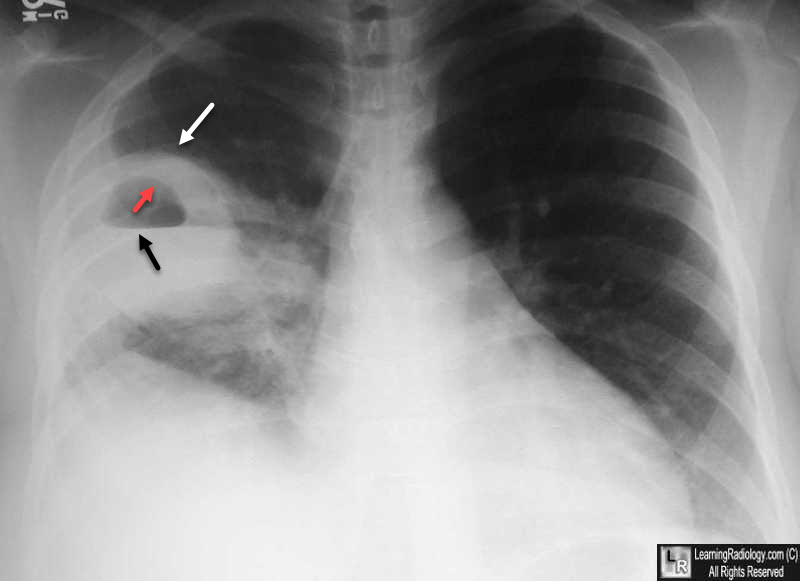

Q.26. A patient presented with sudden chest pain and dyspnea, tactile vocal fremitus and chest movement is decreased, in x-ray there is decreased pulmonary marking on left side, what is the diagnosis?

Correct Answer : B

A pneumothorax is when air leaks into the space around the lungs, causing them to collapse. This leads to sudden chest pain, difficulty breathing, and signs like decreased tactile fremitus and chest movement on one side, along with specific X-ray findings.